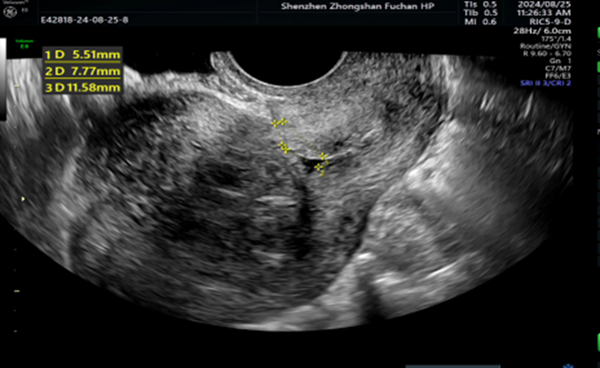

身体里藏了个“山竹”?宫腔镜出手,轻松搞定妇科“麻烦精”!

那天,35岁的李女士慢慢推开诊室门,脸色苍白,走路都有点晃。她把B超单递给我,有气无力地说:“医生,我这半年月经量太大了,现在走几步就头晕,检查说是贫血。”